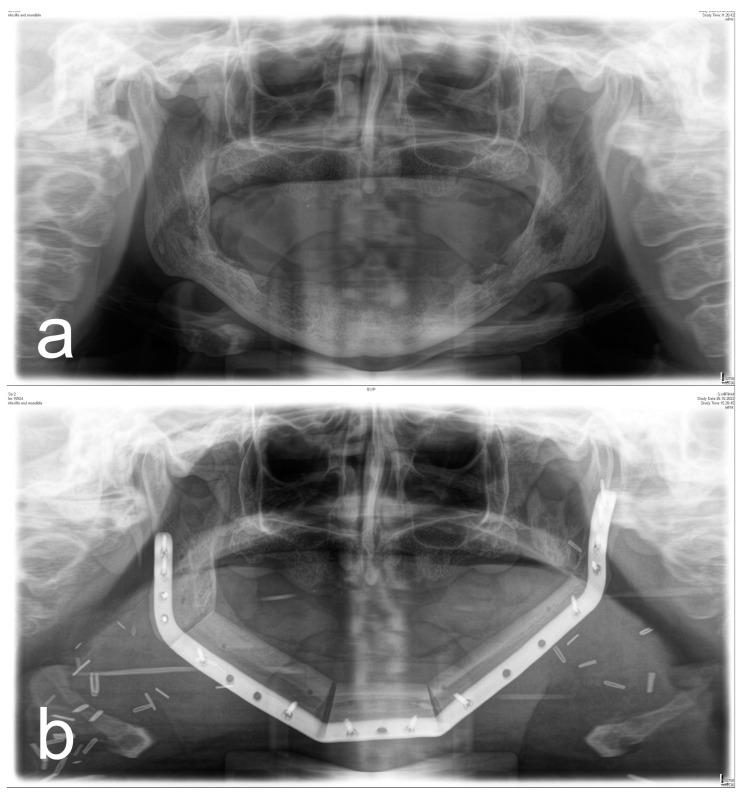

Surgical therapy of osteoradionecrosis of the jaw (ORN) is challenging and requires treatment of the affected hard and soft tissue. To understand how tissue injury after irradiation influences surgical outcomes, the objective of this study was to find out whether (a) bone-related, (b) soft tissue-related, and (c) treatment-related parameters influence the surgical success of patients with ORN. A total of 175 patients (324 lesions) were included in this retrospective, single-center study. All patients were diagnosed with ORN and underwent surgical therapy. The primary outcome was complete soft tissue recovery (mucosa/skin) and the absence of symptoms 3 months after surgery. At the time of follow-up, 58% of patients (189 of 324 lesions) had intact intraoral or extraoral soft tissue. The extent of bone destruction had no effect on treatment success, whereas soft tissue injury due to fibrosis (OR: 0.344; CI 0.142-0.834; = 0.01818) and xerostomia (OR: 0.163; CI 0.064-0.419; = 0.00016) increased the probability of treatment failure. Soft tissue reconstruction with a microvascular graft improved therapeutic success compared to local wound closure (OR: 2.998; CI 1.371-6.555; = 0.006). Thus, for the treatment of ORN, it is extremely important to pay attention not only to the extent of bone destruction but especially to soft tissue defects. Because the extent of soft tissue injury is a predictor for therapeutic success, it should influence the choice of surgical treatment.

颌骨放射性骨坏死(ORN)的手术治疗具有挑战性,需要对受影响的硬组织和软组织进行治疗。为了解放疗后组织损伤如何影响手术效果,本研究的目的是确定(a)与骨相关的、(b)与软组织相关的以及(c)与治疗相关的参数是否会影响ORN患者的手术成功率。本项回顾性单中心研究共纳入了175例患者(324个病灶)。所有患者均被诊断为ORN并接受了手术治疗。主要结局是术后3个月软组织完全恢复(黏膜/皮肤)且无症状。在随访时,58%的患者(324个病灶中的189个)口腔内或口腔外软组织完整。骨破坏程度对治疗成功没有影响,而纤维化导致的软组织损伤(OR:0.344;CI 0.142 - 0.834;P = 0.01818)和口干(OR:0.163;CI 0.064 - 0.419;P = 0.00016)增加了治疗失败的可能性。与局部伤口缝合相比,采用微血管移植进行软组织重建可提高治疗成功率(OR:2.998;CI 1.371 - 6.555;P = 0.006)。因此,对于ORN的治疗,不仅要关注骨破坏程度,尤其要关注软组织缺损,这极为重要。由于软组织损伤程度是治疗成功的预测指标,它应影响手术治疗的选择。